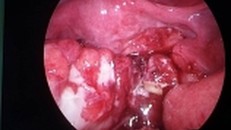

Bé trai nhập viện sau 2 ngày đau bụng. Qua nội soi, bác sĩ ghi nhận bé bị thủng ruột nhiều nơi do 8 thanh nam châm ở các quai ruột khác nhau hít lại với nhau, tì đè lên thành ruột.